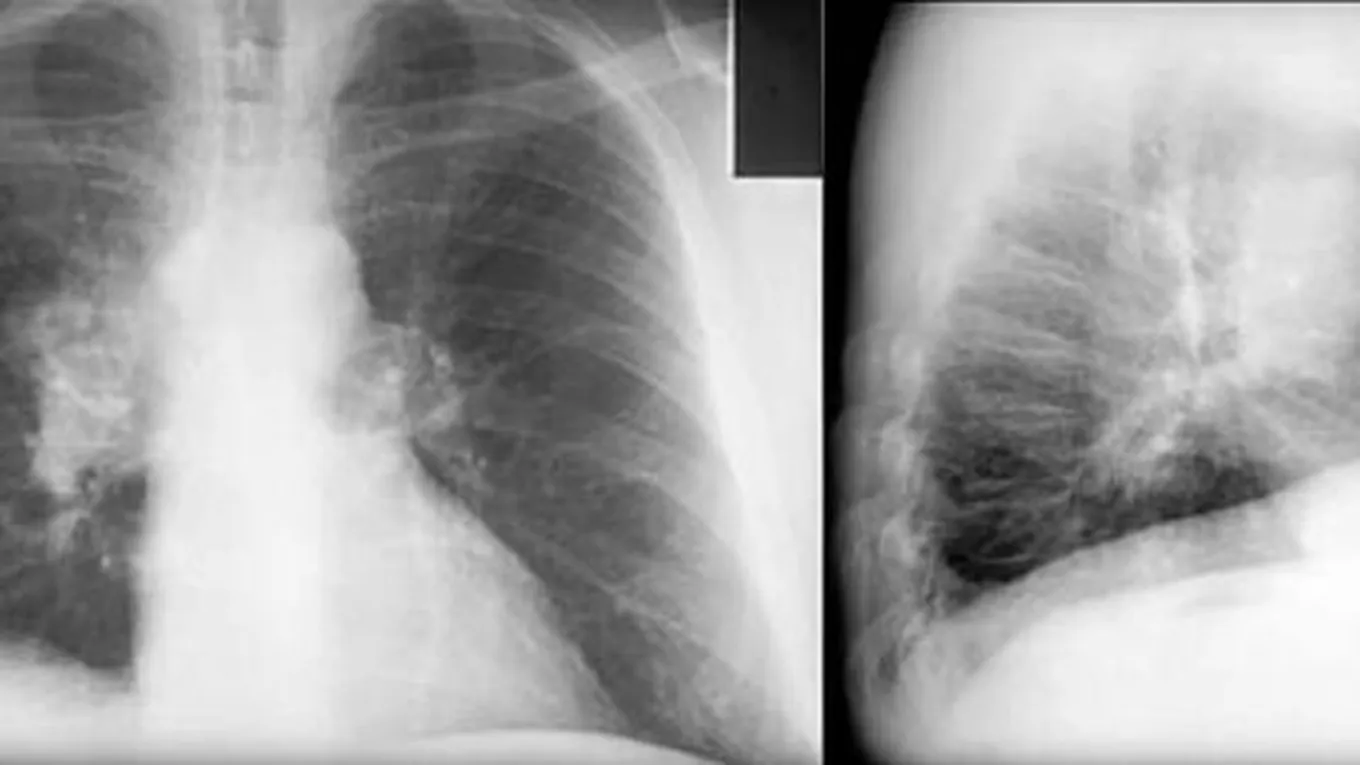

سرطان الرئةلرئة الإنسان القدرة على إصلاح الأضرار ذاتياً، إلا أن تكرار التعرض للضرر يتلف أنسجة الرئة ويهدد استقرارها، وذلك الضرر ينتج من عدة أسباب وعلى رأسها

لرئة الإنسان القدرة على إصلاح الأضرار ذاتياً، إلا أن تكرار التعرض للضرر يتلف أنسجة الرئة ويهدد استقرارها، وذلك الضرر ينتج من عدة أسباب وعلى رأسها التدخين الذي يعد سبباً رئيسياً لسرطان الرئة، حيث إن 90% من المصابين بسرطان الرئة كان التدخين هو المسبب الأول لذلك، وهناك عوامل أخرى تؤدي إلى الإصابة بسرطان الرئة، والتي سيتمّ ذكرها في هذا المقال.[1][2]

أسباب سرطان الرئة

التدخين

يعدُّ التدخينُ المسبب الرئيسي للإصابة بسرطان الرئة، وذلك لاحتواء التبغ على أكثر من 7000 مركب كيميائي، وقد تبين أن العديد منها مسبب للسرطان، ومن أهمّ هذه المواد الكيميائية النتروزامين (بالإنجليزية: Nitrosamines)، والهيدروكربونات الأروماتية متعددة الحلقات (بالإنجليزية: Polycyclic aromatic hydrocarbons)، ومن الجدير بالذكر أنّ احتمالية إصابة الإنسان بسرطان الرئة تزداد كلما زادت كمية استهلاك السجائر، وبالإضافة إلى ذلك فإنّ خطر الإصابة بسرطان الرئة يزيد عند الأشخاص الذين يتعرضون للتدخين السلبي، وهو استنشاق رائحة الدخان التي يدخنها أشخاص غيرهم.[3]

ومن الجدير بالذكر أنّ خطر الإصابة بسرطان الرئة يرتفع مع زيادة كمية الدخان التي يدخنها الإنسان خلال اليوم، وكمية السجائر التي يستهلكها، فعلى سبيل المثال إذا استمر شخص في التدخين مدة 30 سنة يكون أكثرعرضةً للإصابة بسرطان الرئة من شخص استمرّ بالتدخين مدة 10 سنوات، وتجدر الإشارة إلى أنّ الأشخاص الذين يدخنون علبتين أو أكثر من السجائر في اليوم، تكون احتمالية وفاتهم تقارب شخصاً بين كل سبعة أشخاص، وبالرغم من ذلك فليس هناك حدٌّ آمنٌ لاستخدام الدخان، فحتى التعرض لمستويات منخفضةٍ منه قد يكون خطراً، وتجدر الإشارة إلى أنّ خطر الإصابة بسرطان الرئة ينخفض عندما يتوقف الإنسان عن التدخين، وذلك لأنّ خلايا جديدة تنمو في الرئة لاستبدال الخلايا التي تعرضت للضرر.[3]